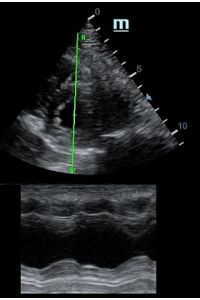

Оценка кооптации нижней полой вены ещё никогда не была такой простой и точной, никаких лишних деталей, просто устанавливаем клипер по анэхогенному участку.

Оценка сокращения сегментов левого желудочка на глаз постепенно уходит в прошлое. Если в приборе нет функции радиального или лонгитудинального стрейна, на помощь опять может прийти Free Xros. Утолщение более 5 мм в систолу – нормальное сокращение, 2-5 мм гипокинез, истончение в систолу – дискинез.